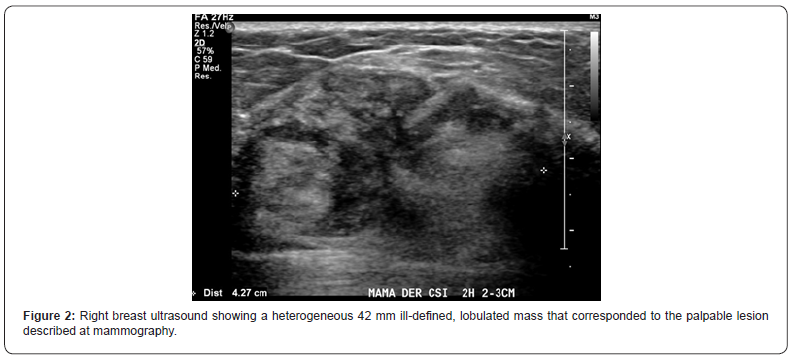

We present the case of a healthy 37 years-old women, with self-detected right breast nodule with 6-months evolution, that was progressively growing and sensitive at touch, associated with erythema and pruritus. She had a familial history of two cousins with breast cancer. At physical exam, there was a hard tumor of approximately 60 x 50 x 30mm at the upper quadrants union (UQU) of the right breast and another 20mm nodule, difficult to separate from the bigger tumor, toward the upper- outer quadrant (UOQ). She was studied with a contrasted mammography that showed a 45mm round-shaped nodule with spiculated edges and early enhancement with contrast, at the UQU (BIRADS-5) and a second 22mm well delimited and moderate enhancing nodule at the upper outer quadrant (UOQ) of the right breast (Figure 1) without invasive-suspected lesions at the left breast. The breast ultrasound demonstrated a 42mm heterogeneous, lobulated mass with imprecise limits and hypoechoic central portion associated with microcalcifications at the UQU of the right breast (Figure 2), a solid oval-shaped well delimited and vascularized 15mm nodule at the UOQ (Figure 3). There was also a 10mm solid-cystic lesion at the inner-quadrants union (IQU) of the left breast (Figure 4). A core biopsy of the two right breast masses was then performed, demonstrating a biphasic fibro-epithelial lesion. The patient underwent a partial bilateral mastectomy of the three lesions, two of them previously marked under ultrasound guidance. The definitive biopsy demonstrated that the lesion of the UQU of the right breast - hour 12, corresponded to a fibromatosis (Figures 5 & 6), and that the other lesion of the UOQ of the right breast was a phyllodes tumor with signs of benignity (Figure 7). In the left breast, an intraductal papilloma was found (Figure 8). The case was discussed at the Oncologic Committee, deciding to follow-up the patient at 6 months with breast ultrasound and contrasted mammography and to offer chronic treatment with celecoxib.

Clinically it presents as a firm, painless or slightly painful mass, sometimes with retraction of the skin or nipple, without discharge or palpable axillary adenopathies. In mammography, it is usually confused with breast cancer due to its irregular shape with spiculated margins, just as in ultrasound, where it is seen as a poorly defined hypoechoic lesion with posterior acoustic shadow and an echogenic ring [9]. The diagnosis is confirmed by core biopsy of the lesion.